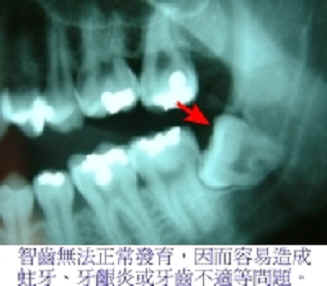

【阻生牙